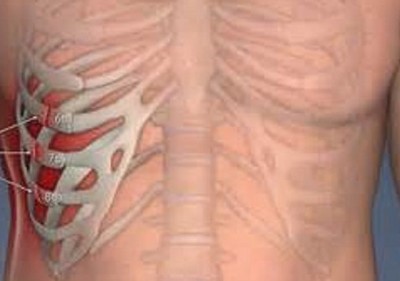

Среди всех травм грудной клетки наиболее часто встречается перелом ребер. Переломом ребер называется нарушение целостности хрящевой и/или костной части. Чаще ломаются 6-9 ребра. Как правило, переломы без осложнений не нуждаются в иммобилизации и значительных врачебных вмешательствах.

В среднем переломы ребер составляют 15% от всех видов повреждений костей. Механизм травмы при данной патологии может быть как прямым, так и непрямым. Примером непрямого механизма является перелом ребер в боковых отделах при сжатии грудной клетки в передне-заднем направлении. Ввиду того, что ребра хорошо соединены друг с другом, смещение отломков в значительных объемах не происходит.

Выделяют так называемые окончатые переломы, которые характеризуются переломом ребра в нескольких местах, что приводит к потере его меньшей части. Эффективным методом лечения в этой ситуации является остеосинтез, который проводится при помощи специального аппарата, благодаря которым фиксируется свободная часть. Посредством сшивания таким образом даже половины сломанных ребер по двум линиям обеспечивается хорошая фиксация подвижного сегмента.